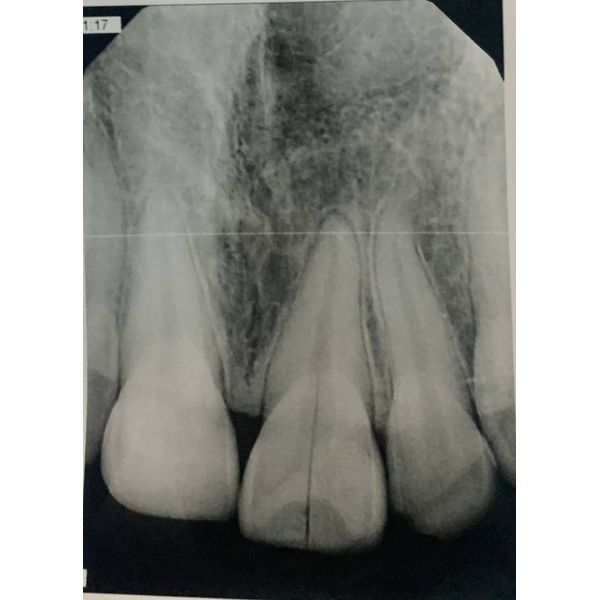

На компьютерной томографии в области потерянного зуба костный дефект не обнаружили, был заметен след восстановления костной ткани, отчётливо видны трабекулы (нормальная структура кости).